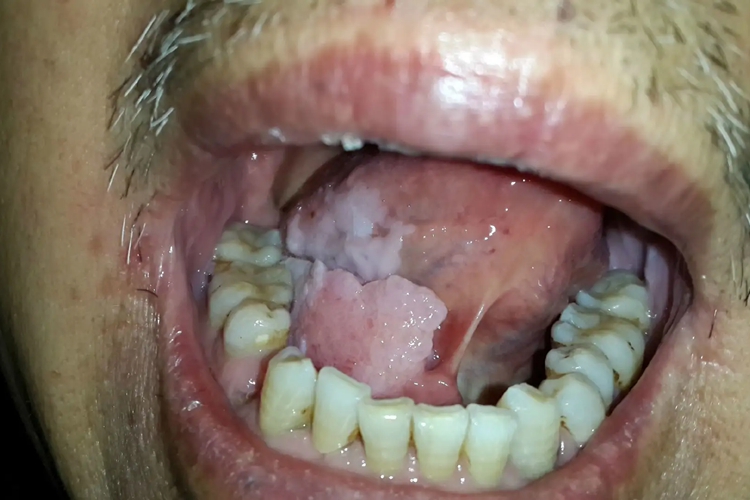

舌乳头状瘤:舌乳头状瘤质软、有蒂、呈丛状的指状突起,或为无蒂的圆顶样病损,表面呈结节、乳头状或疣状。

舌恶性肿瘤即舌癌,疼痛是最常见症状。随疾病发展,疼痛转为剧烈,可放射至耳颞部。检查可见边界不清、基底浸润、触痛明显、伴有坏死的溃疡性肿块。当肿瘤侵犯舌内、外肌时,可出现不同程度舌运动受限,影响语言、咀嚼和吞咽功能。